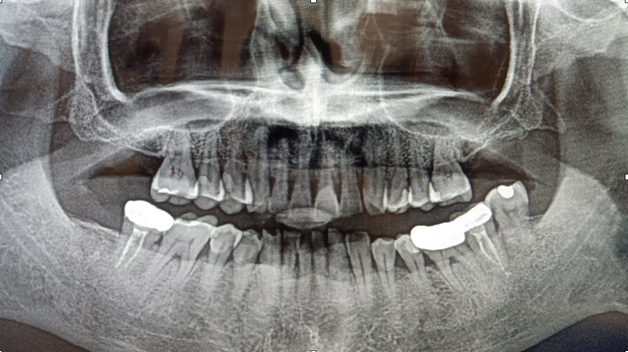

Panaromic Radiograph

- Bruxism (Teeth grinding during sleep)

- Diet (acidic drinks)

- Toothbrushing right after acid exposure

- Erosion severity: ACE Class Class III

- Reduced occlusal vertical dimension

- Mild crowding of lower anterior teeth